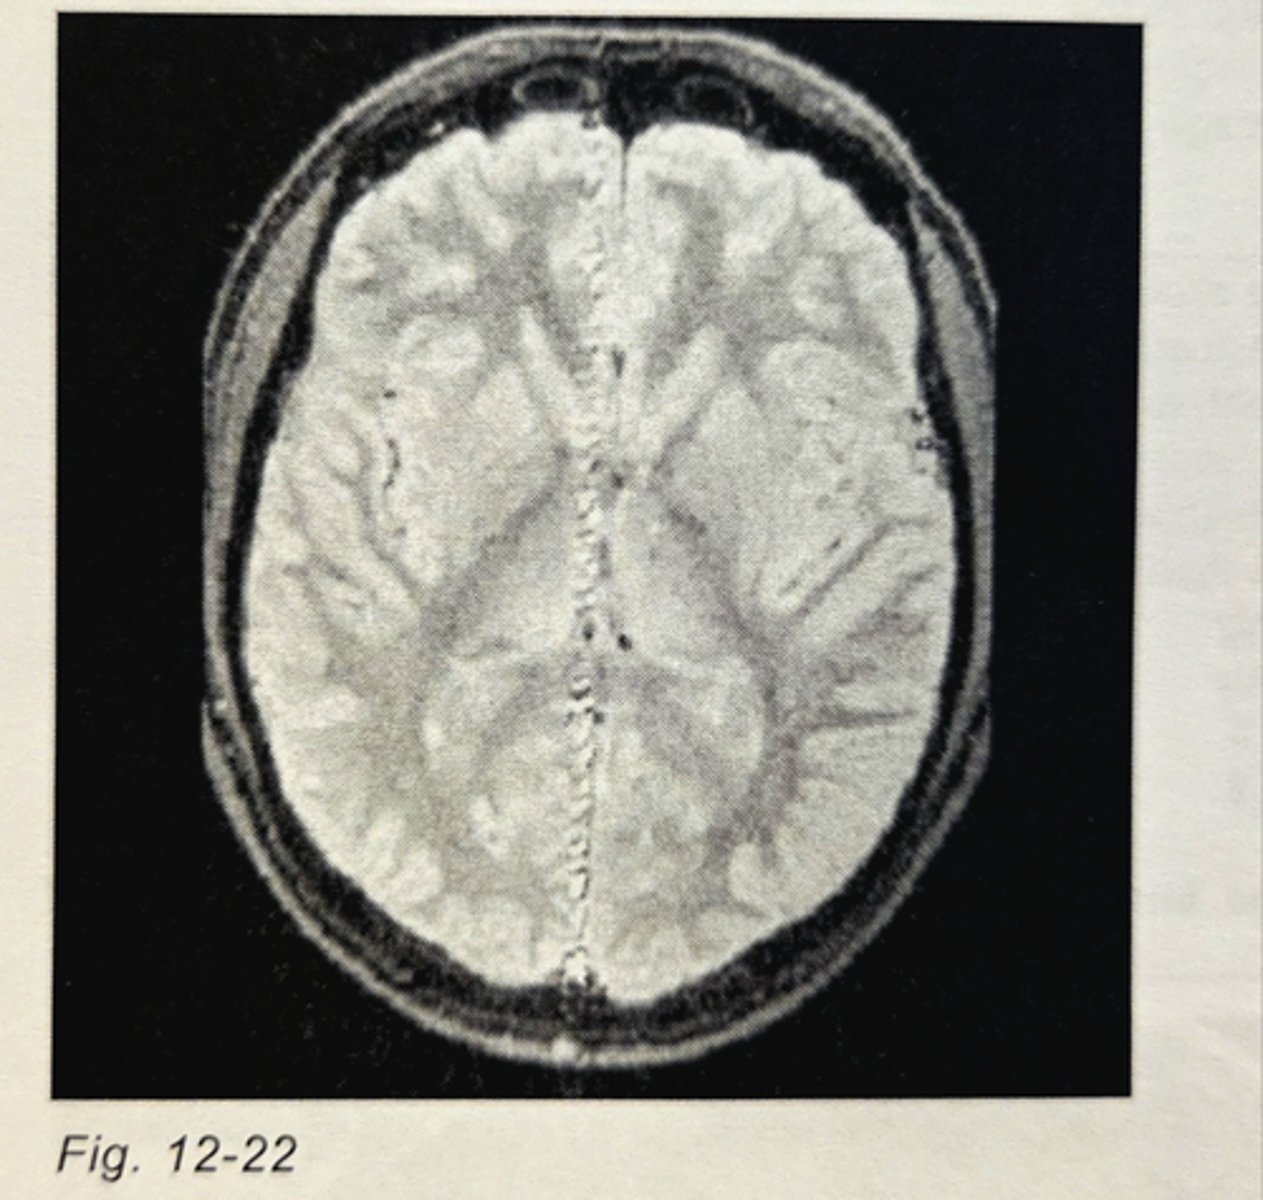

____________________ would NOT help to reduce the severity of flow artifacts in T2-weighted images of the brain:

A narrower receiver bandwidth

If the frequency and phase directions were swapped, but all other parameters remained constant, and the scan was repeated, the flow artifact in Fig. 12-22 would:

extend horizontally across the posterior aspect of the brain